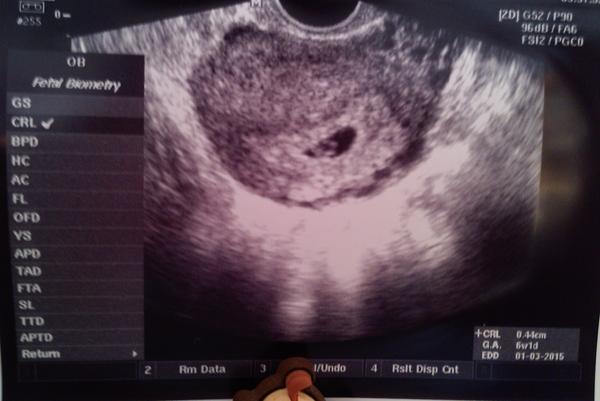

Tak se hlásím z kontroly. Jsme 6+1 a máme srdíčko 🙂 večer nahraju fotečku 🙂 Teď jdeme s manželem ven, máme výročí. Tak to krásně vyšlo dneska 🙂

Holky, díky moc. Kéž by to vyšlo. Ovlivnit to stejně nemůžu, nezbývá než čekat a doufat 🙂 Dnešní výročí jsme si fakt užili, jeli jsme se projít kolem přehrady a pak na oběd do restaurace, kde jsme měli svatební hostinu, tak jsme zavzpomínali, pak na zmrzku a na návštěvu k rodičům... prostě příjemný den. Navíc vyšlo krásné počasí. Ale nejlepší zážitek byl stejně ráno, když jsem na utz viděla blikat to malinkaté srdíčko. Tady je fotka toho našeho bojovníčka... zatím jen 0,44cm.... 🙂